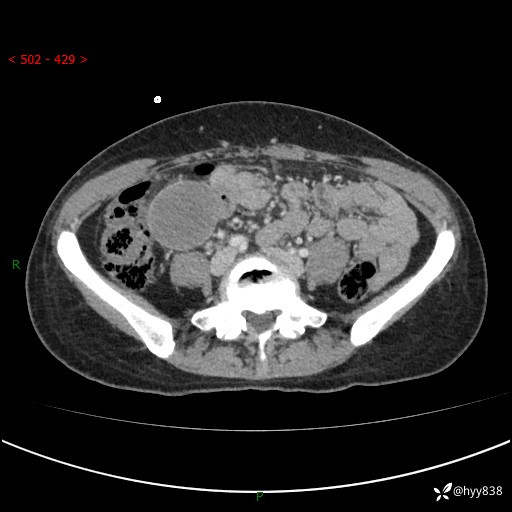

现病史:患者自诉于1周前无明显诱因出现剑突下间断性隐痛,尚可忍受,不向其它部位放射,无恶心呕吐、腹泻便秘等不适,于当地市第二人民医院就诊,行CT结果示:1.右中腹占位,间叶组织来源可能2.小肠梗阻3.盆腔积液4.腹腔积液5.副脾6.肝囊肿;于荆州二医行抗炎,抑酸,护胃,补液等对症支持治疗;患者病情好转,今为求进一步诊治,遂来我院门诊就诊,门诊以“腹腔肿瘤”收入院。 起病以来,患者精神、睡眠、饮食一般,大小便正常,近期体力体重无明显改变。

腹部CT增强(外院平扫)